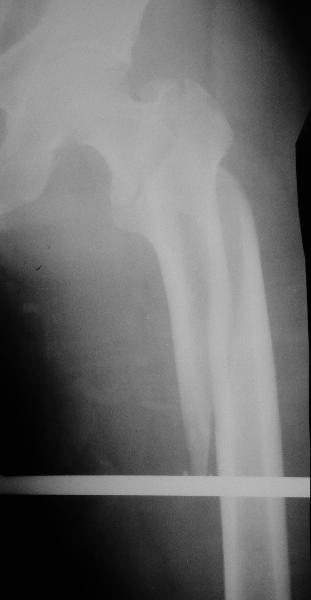

Дорогие коллеги,Как правильно определить такой перелом по классификации AO?

Как два отдельных или есть один соответствующий код? Фиксировать-то оба можно одним фиксатором...

Как раз недавно у меня был примерный случай: больному 36 лет, поступил ночью, травма в результате мотоциклетной аварии, кроме чрезвертельного и спирального перелома левого бедра имеется переломы костей предплечья с этой же стороны. Скелетное вытяжение, а на следующий день больной про оперирован на ортопедическом столе с дистракцией. Чтобы не расколоть чрезвертельный перелом провели временную спицу ближе к переднему кортексу, из малого разреза костодержатель для репозиции, а фиксацию провели антиградным штифтом. Этапы операции на снимках.